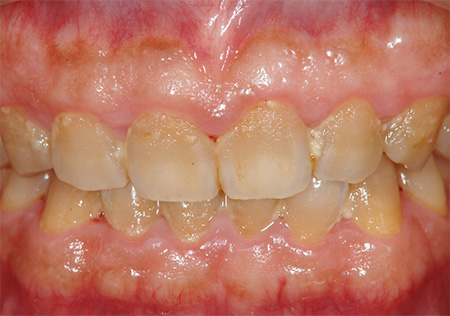

日本国民の80%が歯周病

歯周病というのは、なかなか厄介な病気です。重症度は様々ですが、日本国民の80%が歯周病と言われています。また40代以降の歯を失う原因のほとんどが歯周病です。

いかに歯を失わず、自分の歯でご飯を噛むことができるようにし続けるのは、歯周病にならないようにするかにかかってています。